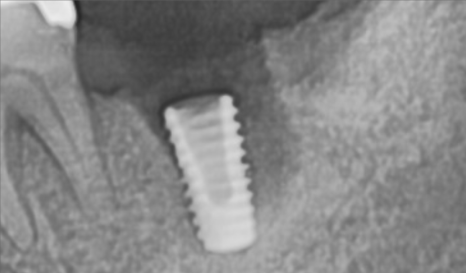

CT상으로 봐도 잘 들어갔군요.

주변부 뼈의 양도 골질도 매우 괜찮습니다.